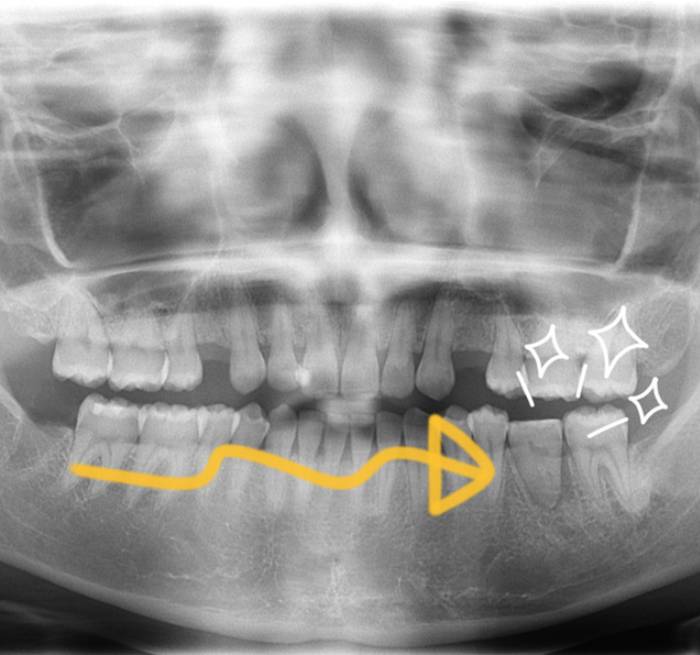

Tooth transplantation歯の移植(自家歯牙移植)

ご自身の歯を再活用する治療

不要な親知らずなどを他の部位に移植する「自家歯牙移植」にも対応しています。

インプラント以外の選択肢として有効で、10代〜30代までの患者様に適応されることが多い治療法です。

※右下の親知らずを左下6番に移植